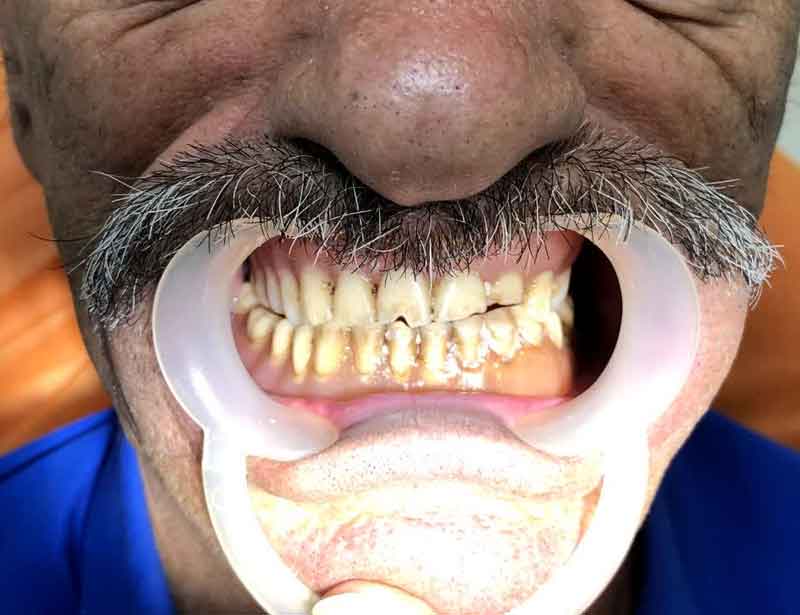

نمونه کارهای قبل و بعد از تحویل پروتز فک بالا و پایین دندان پزشکی رایان

قبل از تحویل پروتز فک بالا و پایین

بعد از تحویل پروتز فک بالا و پایین

نمونه کارهای قبل و بعد از تحویل پروتز فک بالا و پایین دندان پزشکی رایان

نمونه کارهای قبل و بعد از تحویل پروتز فک بالا و پایین دندان پزشکی رایان

قبل از تحویل پروتز دندان

بعد از تحویل پروتز فک بالا و پایین دندان